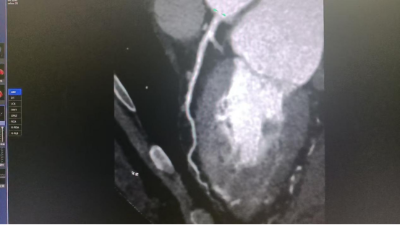

该系统的高分辨率成像技术可清晰显示亚毫米级病变,对早期肺癌、冠状动脉斑块、微小肿瘤等检出率显著提升,使“早发现、早干预”成为可能。结合智能定量分析功能,为肿瘤良恶性鉴别、心血管风险评估提供客观数据支持。